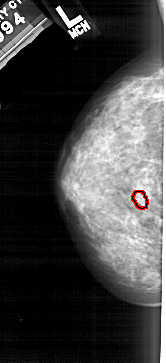

A_1897_1.RIGHT_CC

RIGHT_CC LINES 4906 PIXELS_PER_LINE 2236 BITS_PER_PIXEL 12 RESOLUTION 43.5 NON_OVERLAY

FILE: A_1897_1.LEFT_CC.OVERLAY

TOTAL_ABNORMALITIES 1

ABNORMALITY 1

LESION_TYPE CALCIFICATION TYPE PLEOMORPHIC DISTRIBUTION CLUSTERED

ASSESSMENT 4

SUBTLETY 3

PATHOLOGY MALIGNANT

TOTAL_OUTLINES 1

BOUNDARY